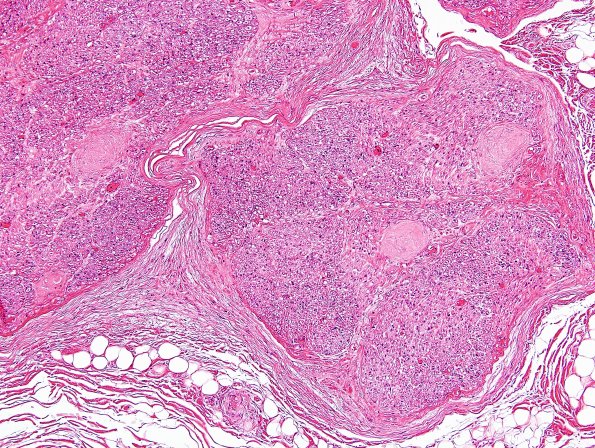

Washington University Experience | PERIPHERAL NEUROPATHY | 1 NORMAL NERVE ANATOMY | 8 Renaut bodies | 6A1 Renaut body (CIDP, Case 6) L Brachial Plexus H&E 7

6A1-3 This nerve was biopsied with a suspicion for CIDP but showed multiple rather dense RB instead. (H&E)